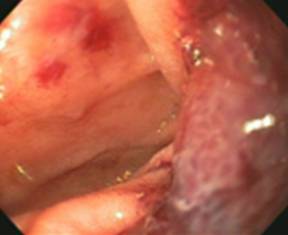

Initial laboratory tests were all within normal limits. She initially underwent a computed tomography (CT) scan of the abdomen that showed a duodenal obstruction at the ligament of Treitz (Figure 1). The patient then underwent an upper endoscopy that demonstrated a hemi-circumferential erythematous non-obstructing mass in the duodenum (Figure 2). Biopsies were taken that showed active enteritis and features of ischemia but no evidence of malignancy. Further blood testing was remarkable for a normal urine 5-hydroxyindoleacetic acid (5-HIAA) level and a slightly elevated chromogranin-A level 53 ng/mL (reference range: 0-50 ng/mL).

Figure 2. Image of the mass from upper endoscopy. |